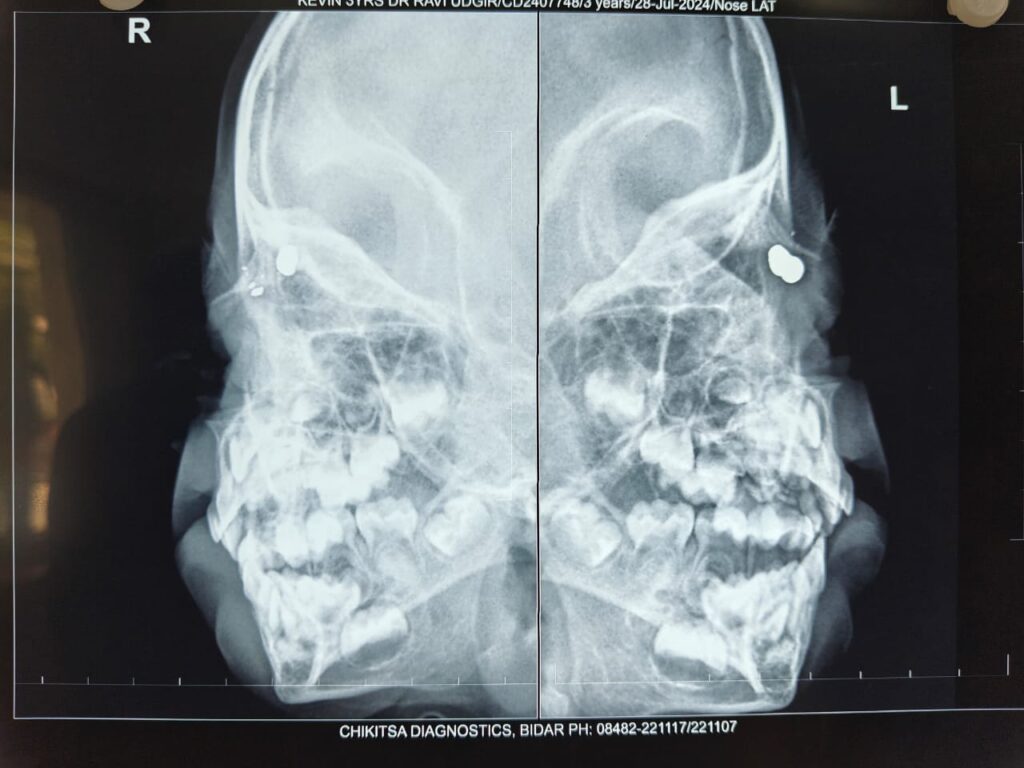

Although initial X-rays at a local hospital did not reveal the presence of the pellet and the child was discharged with conservative treatment, the parents noticed a bluish discolouration on the upper eyelid a few days later. This prompted further evaluation and referral to Sankara Eye Hospital, Hyderabad, for specialist care.

Detailed examination and imaging revealed a metallic pellet measuring approximately 7–8 mm lodged extremely close to the eyeball. The child underwent a successful anterior orbitotomy with foreign body removal under general anaesthesia. The procedure was performed by Dr. Sirisha Polkampally, Consultant – Orbit & Oculoplasty and Cataract Surgeon at Sankara Eye Hospital, Hyderabad.

The surgery was technically challenging, as the pellet, though appearing superficial, was deeply embedded in the orbital tissue and located close to the lacrimal drainage system, which is responsible for tear flow. Meticulous precision was required to avoid damage to surrounding structures.

Dr. Sirisha Polkampally added, “The pellet had entered through the nasal root and was gradually moving towards the eye. Careful dissection was essential to remove it safely without affecting vital structures, particularly the lacrimal apparatus.”